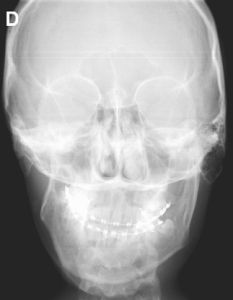

在半側顏面短小畸形的臨床表現中,可累及多個解剖部位且嚴重程度不一,表現為患側面部短小,皮下軟組織薄弱,頦部偏斜,面神經發育不良,面橫裂及外耳畸形等,其中以骨骼畸形以下頜骨發育不良最常見也最重要,嚴重者可累及上頜骨、顴骨、顴弓及顱顳部骨骼,其中下頜骨的畸形是最明顯,而且下頜骨受累的嚴重程度與面部其他部位包括眶部、顴骨、外耳、軟組織的受累程度呈正相關,具體詳述如下:

其他顱面骨骼受累與下頜骨的嚴重程度有關,患側上頜骨的垂直高度縮短,咬牙合平面相應向患側向上傾斜,患側上頜恆磨牙萌出延遲,嚴重者伴有顴骨發育不良,顴弓窄小,甚至缺失,顴部的發育不良與下頜骨髁狀突及升支畸形有直接相關性。乳突可有發育不良,乳突房的氣化程度不一。莖突縮短或缺失。眼眶在各個方向的發育不良不常見,部分患者伴有小眼。患側額骨可表現為平坦,類似於斜頭畸形的表現,但無單側冠狀縫早閉。頸椎畸形包括偏側脊椎發育不全、畸形融合,腦幹扁平。

第一二鰓弓綜合徵此外,下頜骨的畸形會導致上頜骨及其他顱面骨的繼發發育異常,患側咬頜平面向上傾斜,上頜骨的向下生長受限,阻礙了眼眶與上齒槽嵴和鼻梨狀孔區正常的進行性分離,致眶底與上頜牙槽弓的垂直距離縮短,嚴重者伴顴骨發育不全,顴弓的跨距縮短,導致患側外眥與耳屏水平連線距離縮短,所以可以說,下頜骨畸形是半側顏面短小畸形的基石,故矯治下頜骨的畸形也成為治療的關鍵。

患者出生後,畸形是否會呈進行性發展,這也關係到治療時機的選擇。大部分的研究表明,半側顏面短小畸形會隨生長發育有所加重,表現為梨狀孔平面進行性的傾斜,患側下頜角的位置較對側上移,這種進行性加重的程度與下頜骨本身畸形的嚴重程度有關。大部分患者出生時僅有下頜骨的畸形,其咬牙合平面、梨狀孔及眼眶均無明顯的傾斜及不對稱,但隨著雙側的不對稱發育,面部的不對稱呈漸進性加重。兒童時期用肋軟骨重建下頜骨升支及髁狀突後,如重建的升支與對側能同步發育,且開牙合處有牙齒萌出,其咬牙合平面及雙下頜角間的連線不傾斜,但如重建升支沒有與對側同步發育時,其咬牙合平面、雙下頜角間的連線及梨狀孔漸進性傾斜。甚至在早期進行了下頜骨延長術的患者,延長後的下頜骨其生長速度仍不及正常側,隨生長發育也可表現出不同程度的下頜骨升支不對稱及咬牙合平面的傾斜。